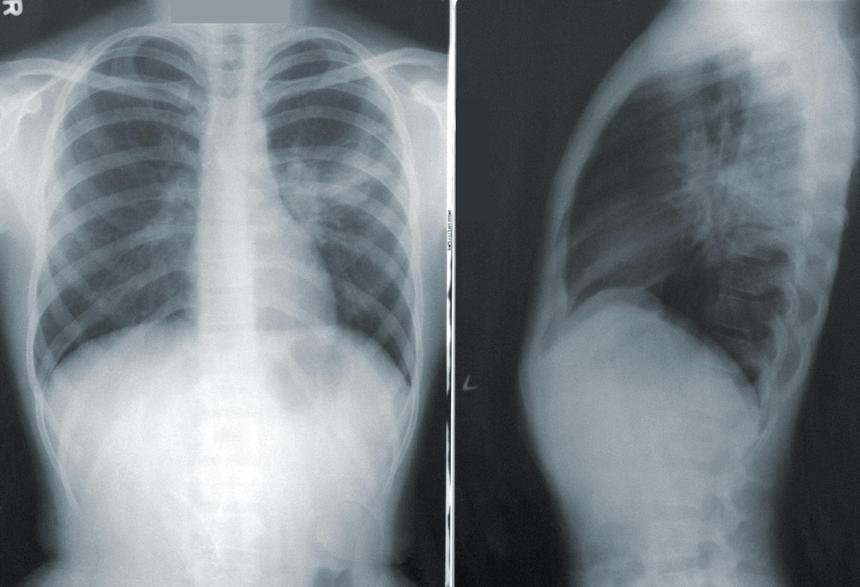

Учёные: работа по ночам повышает риск рака лёгких

Учёные обнаружили важную молекулярную связь между раком лёгких и нарушением циркадных ритмов. Нарушиться они могут, например, из-за работы по ночам.

Из нового исследования следует, что когда циркадные ритмы нарушены, это «включает» ген, известный как HSF1, который может вызывать опухоли лёгких. В целом, лёгкие находятся под жёстким циркадным контролем и кажутся особенно уязвимыми при нарушении биологических часов.